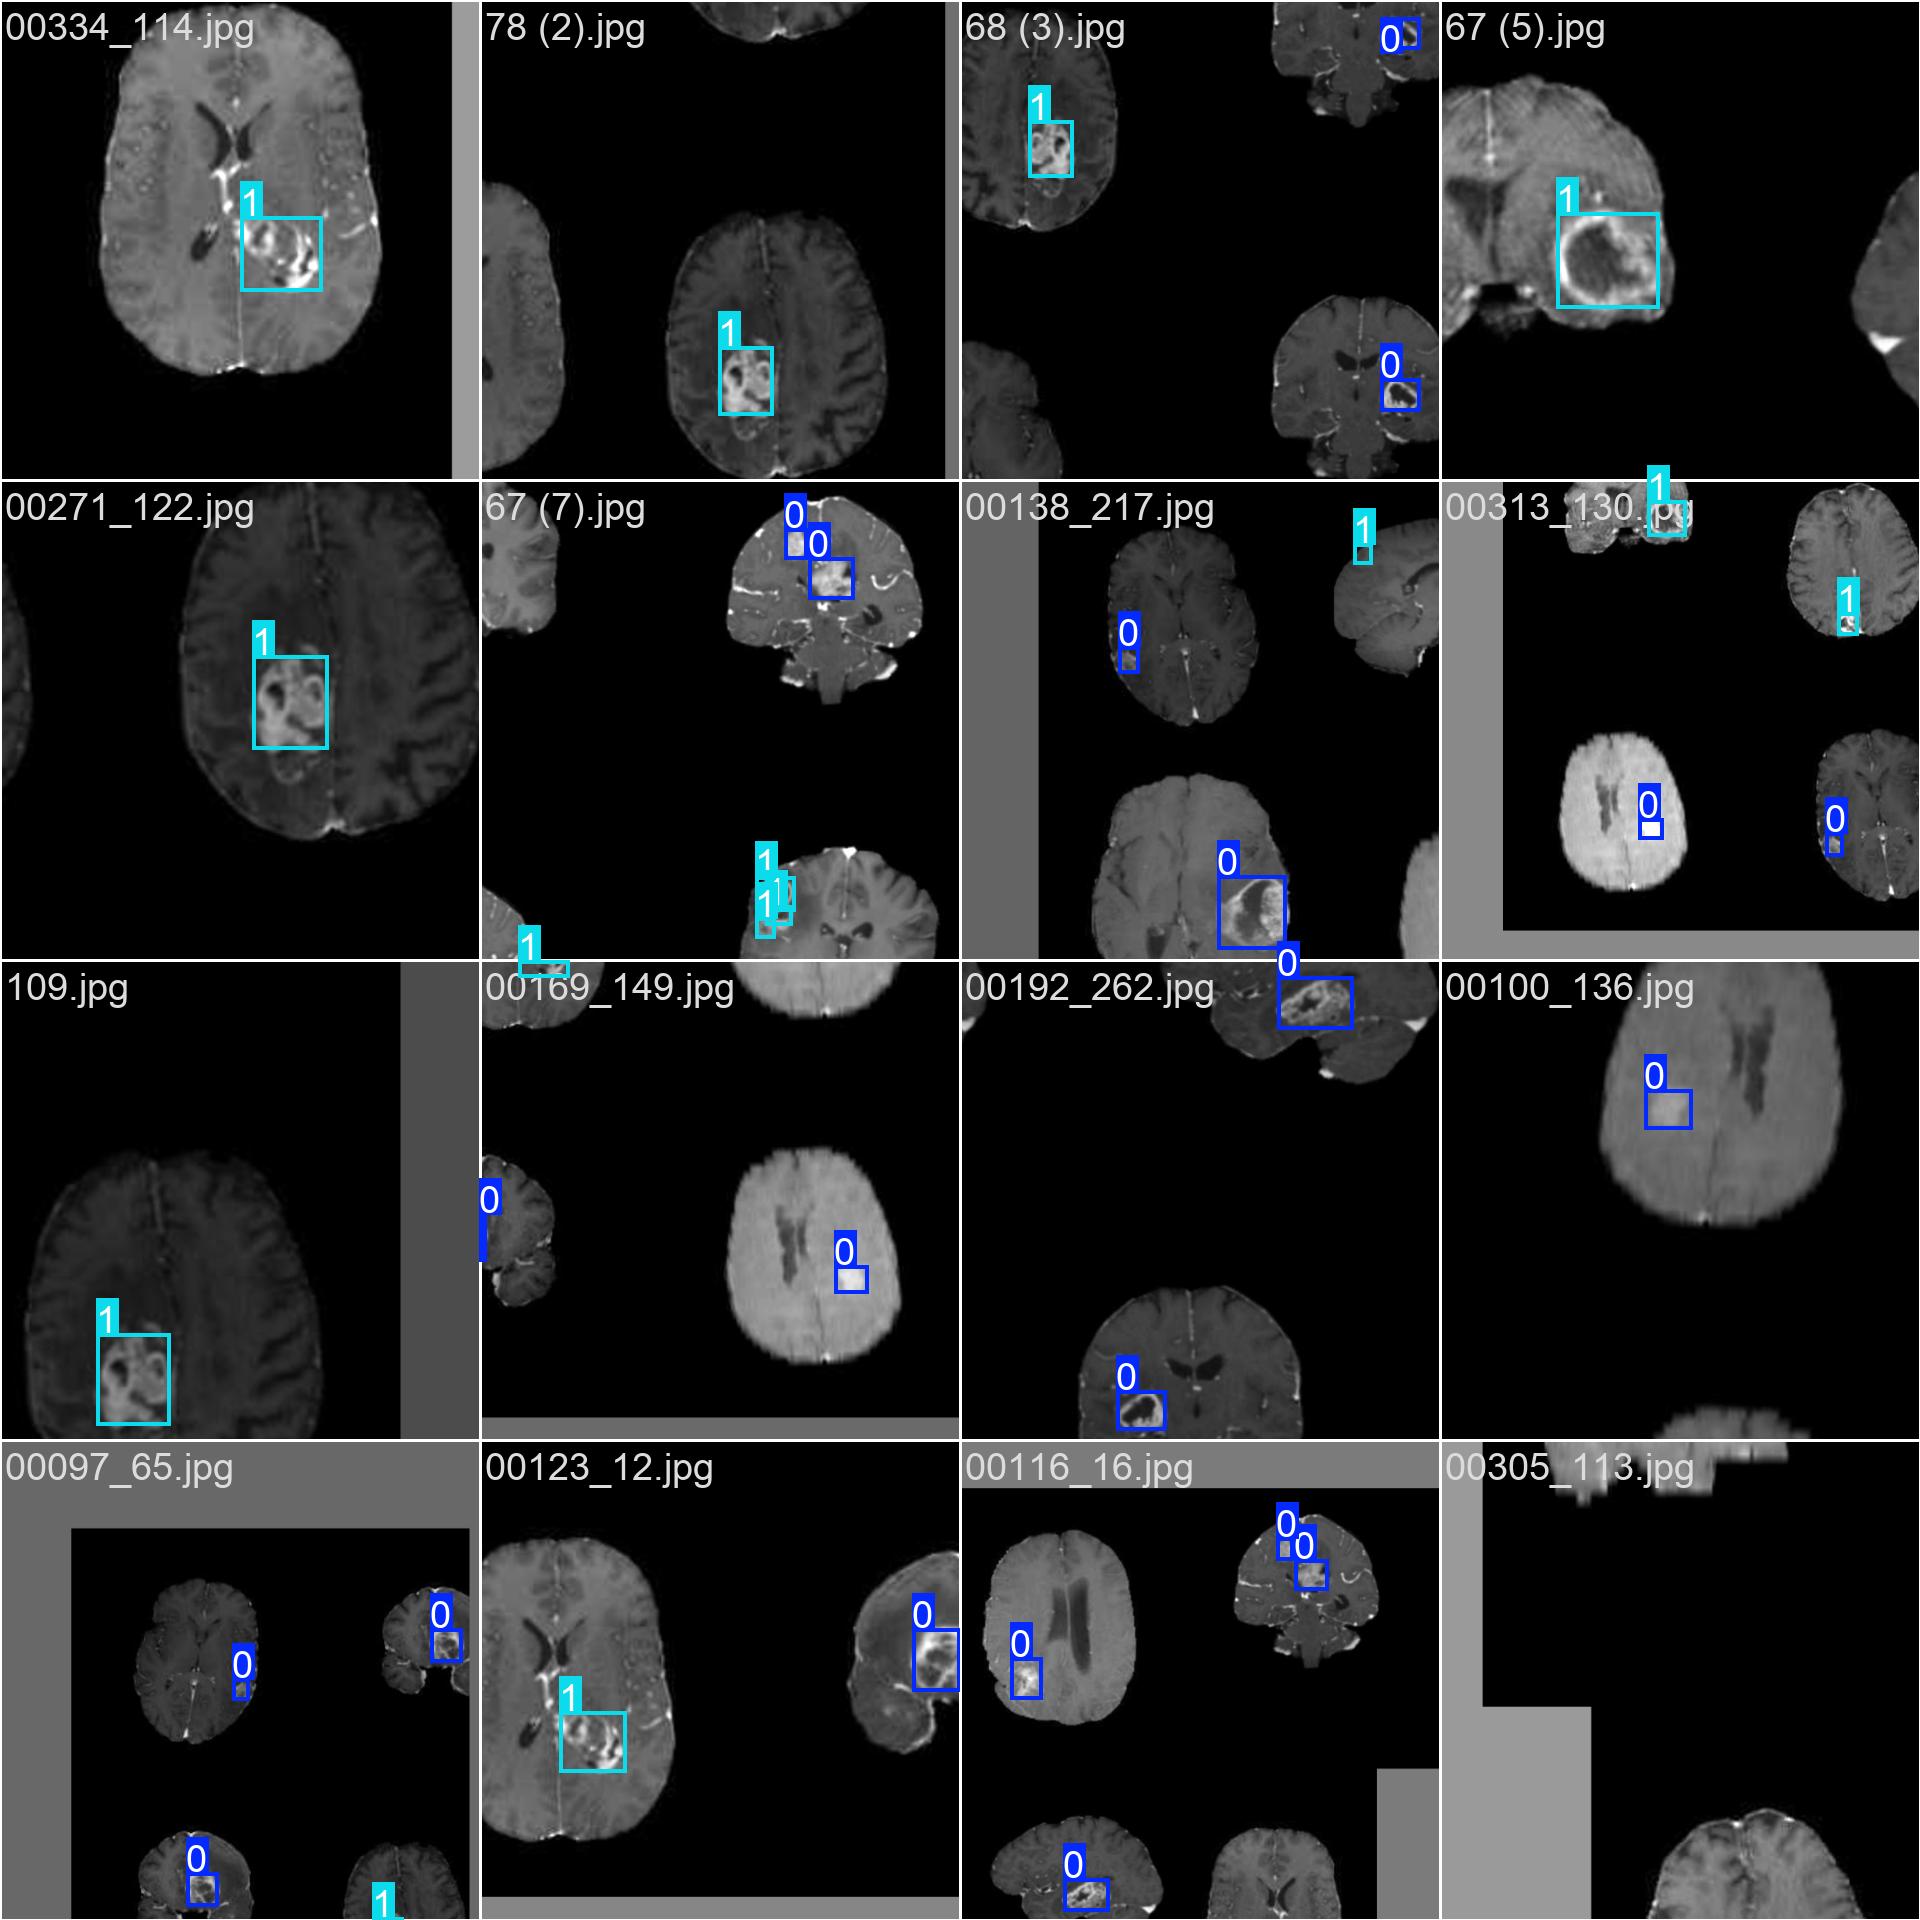

3.2 数据标注

使用标注工具(如 LabelImg, CVAT, Roboflow 等)对图像中的每一个肿瘤区域进行标注。

-

每个肿瘤需框出其边界(Bounding Box)

根据临床标准赋予类别标签:

negative或positive -

标注格式

:YOLO 使用

.txt文件存储标注信息,格式为:

txt<class_id> <x_center> <y_center> <width> <height>所有坐标值都是相对于图像宽高的归一化值(0-1)。

class_id = 0→negativeclass_id = 1→positive